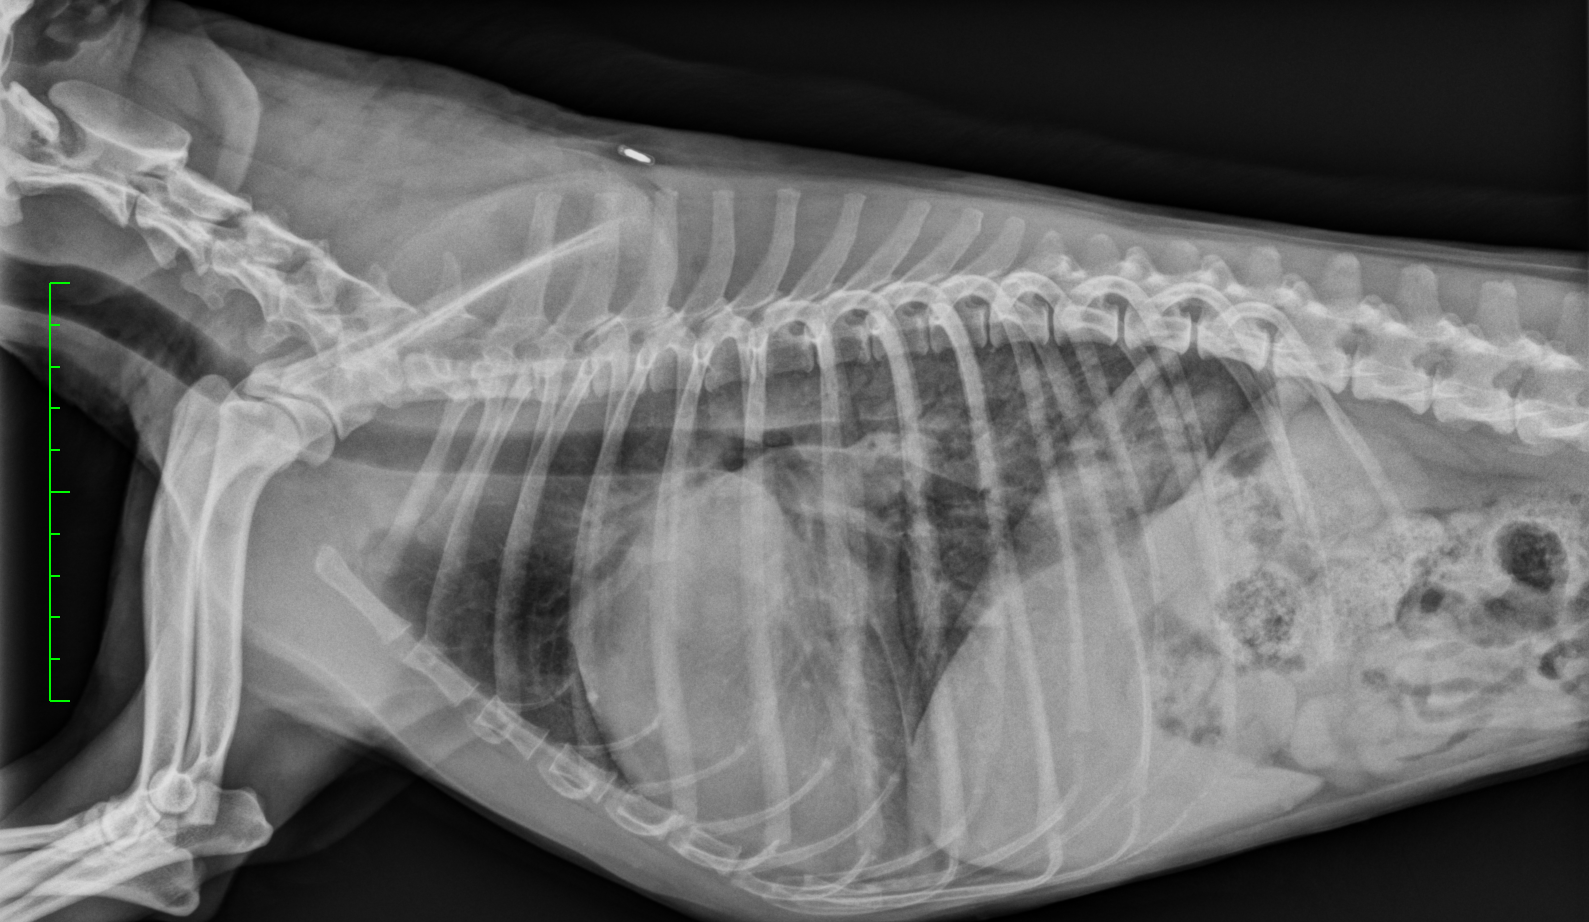

2.12.26: Thorax im Notfall – kein Grund zu hyperventilieren

In diesem Online-Seminar lernen Tierärzt:innen das notwendige Know-how, um Thorax-Röntgenaufnahmen sicher zu interpretieren und zielgerichtete, lebensrettende Maßnahmen zeitnah einzuleiten. Prof. Dr. Patrick Kircher führt Sie durch die wichtigsten Schritte der Thorax-Diagnostik in Notfallsituationen.

Referent: Prof. Dr. Patrick Kircher, Direktor der Klinik für Bildgebende Diagnostik am Tierspital Zürich